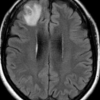

호주 건망증 여성 뇌 속에 8㎝ 벌레 살아서 ‘꿈틀’…

비단뱀 기생 회충…“인체내 발견은 최초 보고사례”야생풀 섭취 이력…사람·짐승 공유지의 위험성 재확인 건망증과 우울증을 앓던 64세 호주 여…